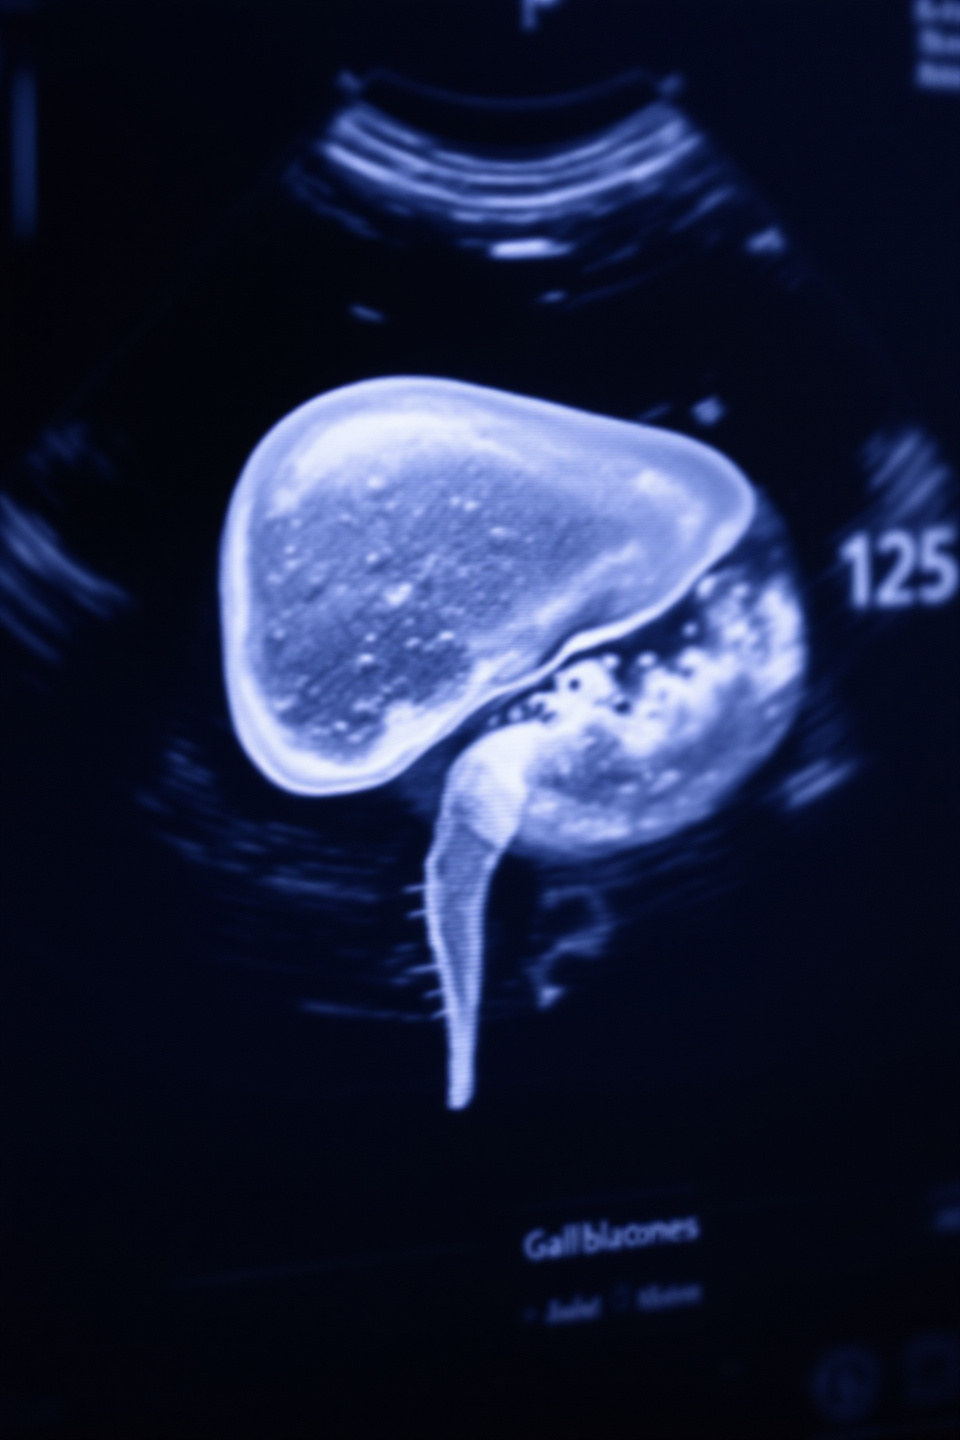

📌 1. 담낭 질환: 통증의 가장 흔한 원인

담낭은 간에서 생성된 담즙을 저장하고 필요할 때 소장으로 방출하는 역할을 합니다. 하지만 담낭이 제대로 작동하지 못하면 통증을 유발하는데요, 특히 담석증과 담낭염이 주요 원인입니다.

- 담석증: 담즙 내 콜레스테롤이나 빌리루빈이 결합하여 딱딱한 결석(담석)을 형성합니다.

- 담낭염: 담석이 담낭관을 막거나 세균 감염으로 인해 담낭에 염증이 생깁니다.

- 검진 필요:

- 담낭 초음파 검사나 CT 촬영으로 담석 여부를 확인하세요.

- 증상이 심한 경우 전문의의 진단이 필요합니다.

- 치료 옵션:

- 담석이 작다면 약물로 치료 가능하지만, 크거나 염증이 심하면 담낭 절제술이 필요할 수 있습니다.